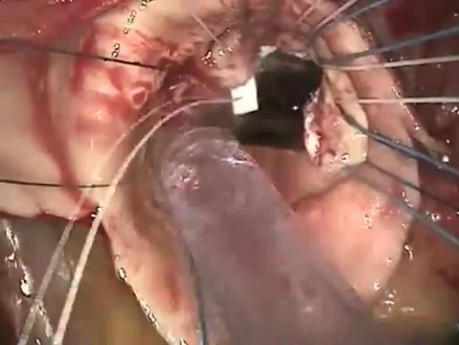

Materiał przedstawia zabieg rekonstrukcji opuszki i aorty wstępującej. Zabieg ten zalecany jest wśród pacjentów kwalifikowanych do zabiegu operacyjnego z powodu tętniaka aorty wstępującej i z niedomykalnością...

Rekonstrukcja opuszki i aorty wstępującej

Film prezentuje zabieg rekonstrukcji opuszki i aorty wstępującej. Zabieg ten zaleca się pacjentom kwalifikowanym do zabiegu operacyjnego z powodu tętniaka aorty wstępującej i z niedomykalnością zastawki...